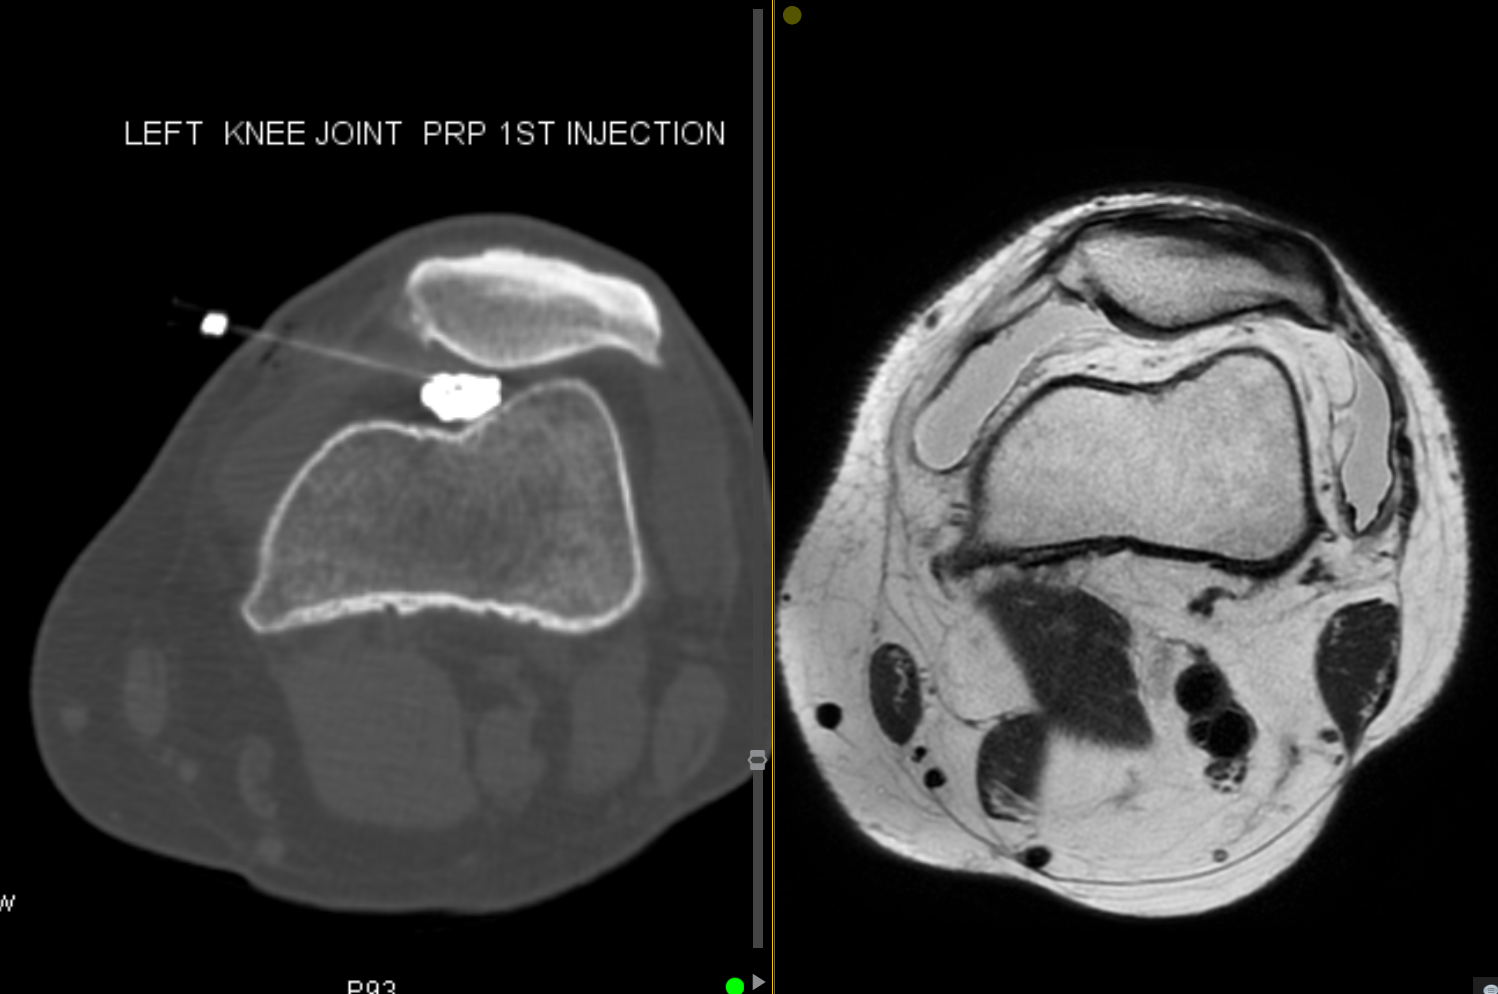

Knee osteoarthritis is a common and debilitating condition affecting millions of Australians.

Interventional treatment options include knee joint steroid injections, PRP injections, hyaluronic acid injections, genicular artery embolisation, genicular nerve block and genicular nerve ablation.

Given the multitude of treatment options available, our specialists can tailor a custom treatment regimen for you at the time of consultation.

PRP Injection

Platelet rich plasma (PRP) is obtained by drawing a patient's blood and spinning it down in a centrifuge. The platelet and plasma layer can be injected into a joint or tendon and has healing properties based on a small amount of stem cells in this layer. The best targets for PRP include the large joints of the body and tendons.